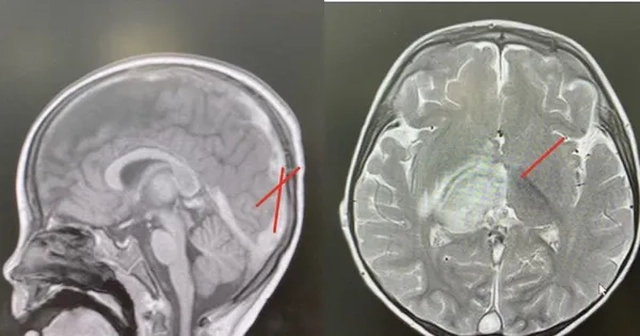

Kết quả kiểm tra hình ảnh cho thấy huyết khối và tình trạng tổn thương não ở bệnh nhi (ảnh: BVCC)

Các kết quả chẩn đoán hình ảnh cho thấy bé bị nhồi máu não vùng đồi thị, kèm phù não và huyết khối lan rộng trong hệ thống tĩnh mạch não – từ vỏ não, xoang tĩnh mạch nội sọ cho đến tĩnh mạch cảnh chung bên trái. MRI cũng ghi nhận xuất huyết trong não. Đây là dấu hiệu điển hình của huyết khối tĩnh mạch nội sọ (hay còn gọi là huyết khối xoang tĩnh mạch não).